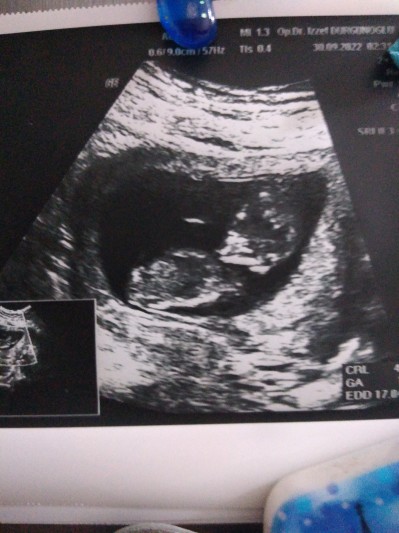

sizce kız mı erkek mi? Daha çok erken biliyorum ama çok merak ediyorum ☺️

Gebelik haftası 13

Rabbim gönlüne göre versin benim de 15.hafta olacak hala öğrenemedim cinsiyeti benimde görüntü bu 14 haftalıkken